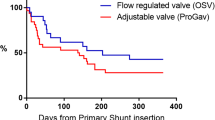

A Etiology of hydrocephalus for 74 infants who received early VPS treatment with a fix differential pressure valve and an adjustable gravitational unit. B Kaplan-Meier analysis referring to a mean follow-up of 63 months after initial VPS insertion showing revision-free shunt survival rates (79% after 12 months, 70% after 24 months) and valve-survival rates (91% after 12 months and 90% after 24 months) for the entire patient collective. C Distribution of Evans ratio and D FOHR before, and latest follow-up data after shunt treatment

Shunt complications and revision surgeries

All patients obtained continuous post-operative clinical follow-up for 24–131 months (mean 63 ± 25.6 months). Twelve months after initial shunt insertion 25 patients (32%) and after 24 months 30 patients (38%) underwent shunt revision surgery (Fig. 2A). During entire follow-up 35 patients (45%) underwent at least one shunt revision surgery (range 0–9 revisions, mean 1.3 ± 2.0). For the 35 revised shunts in total (Fig. 2D) the initial shunt malfunction was related to catheter occlusion (34%), growth-related migration (31%), infection (9%), peritoneal malabsorption (8%), disconnection (6%), development of loculated hydrocephalus or isolated fourth ventricle (6%), skin lesion (3%), and undefined cause (3%). Kaplan-Meier analysis revealed revision-free shunt survival rates of 79% after 12 months and 70% after 24 months (Fig. 1B). Surgical shunt revisions involved the valve in 9 patients (12%) after 12 as well as after 24 months and in 13 patients (18%) at last follow-up after VPS insertion (Fig. 2B). In Kaplan-Meier analysis the revision-free valve survival rates were 91% after 12 months and 90% after 24 months (Fig. 1B). Within the subgroup of revised valves, reasons for initial valve revision were dysfunction due to valve occlusion in 11 patients (85%) and shunt infection in 2 patients (15%) (Fig. 2D). Referring to the entire patient collective 3 patients (4%) experienced early post-operative shunt infection within 30 days after initial shunt insertion, total cumulative shunt infections at any time during the entire observation period occurred in 7 patients (9.5%), and accounted exclusively for patients with IVH-related PHHC.

For pediatric patients it should be of highest priority to aim for a far-sighted and sustainable treatment strategy offering maximal flexibility for optional pressure level adjustments in regard to hydrostatic over-drainage protection. Optimal shunt treatment is focused on a near physiological condition for CSF drainage in regard to the patient’s age, physical constitution, and activity level [22]. Physiological body growth during neonatal, infantile, and juvenile development inevitable leads to various changes especially in hydrostatic parameters and requires the necessity to provide an option for non-invasive adjustment of corresponding shunt-drainage conditions. Considering the vulnerable characteristic of the presented patient collective, our results with revision-free shunt-survival rates of 79% after 12 months and nearly 70% after 24 months enhance the feasibility of this primary treatment protocol even in newborns and infants. Revision-free valve survival for the primary inserted miniNAV and proSA® combination with 90% unrevised valves after 24 months indicate a reliable application in the long term. Shunt malfunction with necessity for revision surgery referred to the well-known and characteristic problems of this patient subgroup regarding vulnerability for infection, growth-related catheter migration, and occlusive dysfunction presumably caused by blood degradation or glial scarring. The rate of performed adjustments (63%) at the time of last clinical follow-up implicates that different subsequent pressure-level alterations in order to adjust CSF drainage for symptom control, sufficient reduction of ventricular enlargement, and stabilization of head growth were conducted to follow an individually adapted treatment protocol. The option to adjust the gravitational unit appears beneficial in our experience even for young infants with limited active vertical mobility. The adjustment option proved increasing implication over the long-term clinical course and physical development from a mainly horizontal towards a predominantly vertical body position. The used valve and shunt technology is only one part of the overall applied therapeutic procedure and early removal of blood constituents together with early and strongly physiological adapted temporizing measures to avoid ependymal loss and glial scarring with extracellular matrix membranes are advocated.